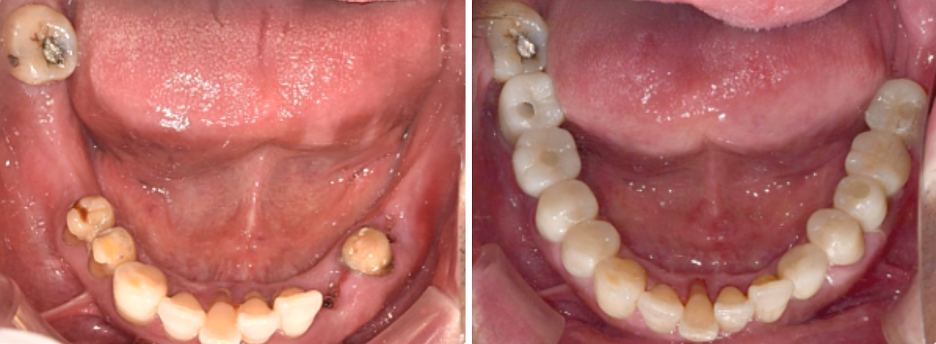

68세 남성

(전) 2021-11-05, (후) 2022-08-26

임플란트/크라운 시술 후

음식 섭취뿐만 아니라, 심미적인 개선으로

삶의 질이 높아진 환자분의 사례